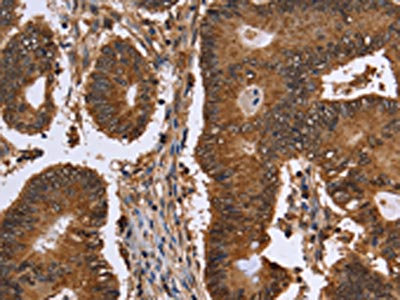

The image on the left is immunohistochemistry of paraffin-embedded Human cervical cancer tissue using CSB-PA569454(FANCF Antibody) at dilution 1/60, on the right is treated with fusion protein. (Original magnification: ×200)